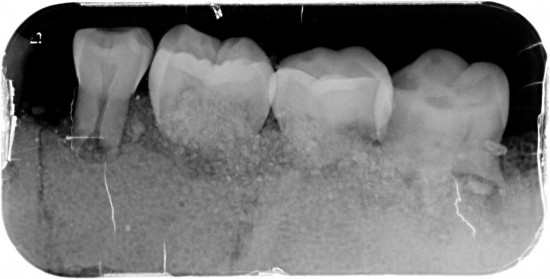

Dit kaakje werd door mijn tandarts grondig bekeken en róntgen foto,s van gemaakt .

Met zijn  langdurige ervaring  uit zijn eigen praktijk. Kunnen namelijk  Molaren verkeerd om zitten. (zie 1ste  molaar linker kaak)

Tevens kunnen er zowel  tanden teveel of te weinig voorkomen .( zie 5 snijtanden ) . De 5de premulaar en hoektand lijken maar een  tand  te zijn , zie rechterkaak. Rontgenfoto wijst echter uit dat het toch 2 aparte tanden zijn .